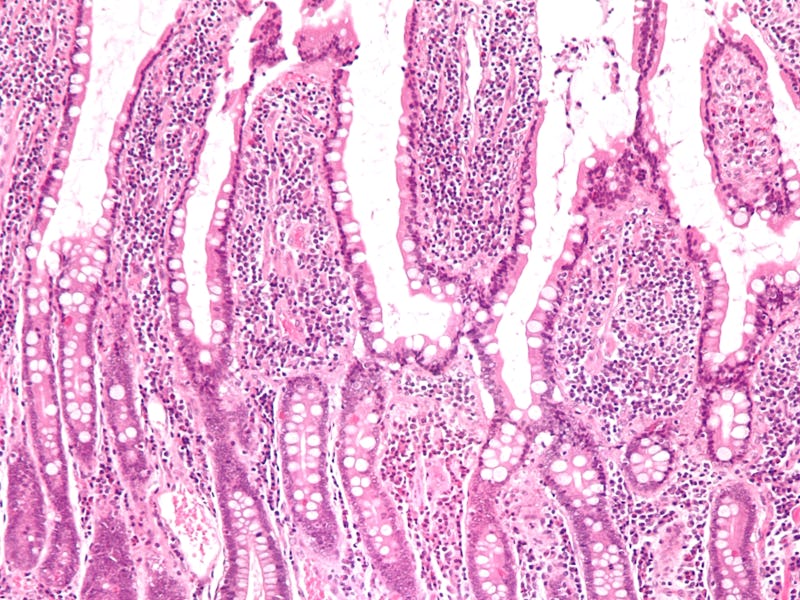

The human intestines are extremely efficient at absorbing nutrients, in large part due to villi — little wiggly protrusions inside the intestinal tract that greatly increase its surface area, making the system far more efficient. Imitating this biological design in a battery therefore makes sense, but it took researchers until now to figure out how to do so. In theory, a lithium-sulphur battery has a far greater energy density, but breaks down too quickly to make its advantage over lithium-ion worthwhile.

Computer rendering of the villi-inspired nanowires.